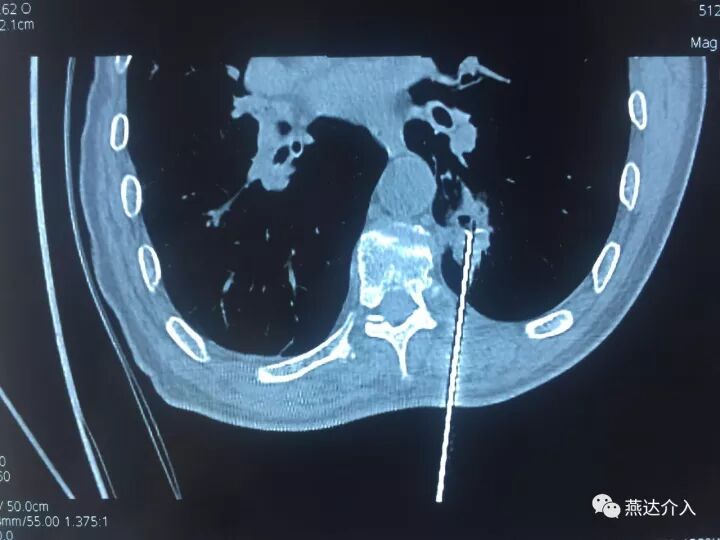

近日燕达医院收治一名肺内占位患者,行PET-CT考虑肺内占位,恶性可能,肺部多发小结节,考虑转移。为进一步明确肺内占位性质,放射介入科予患者穿刺活检,病理证实为肺鳞癌。为治疗肿瘤,决定予患者行肺癌射频消融术。

术中予患者2cm射频针3针消融,术后可见病灶周围晕征出现,肿瘤内可见消融后气化影,消融效果全面完全,术后患者情况良好,无不适。